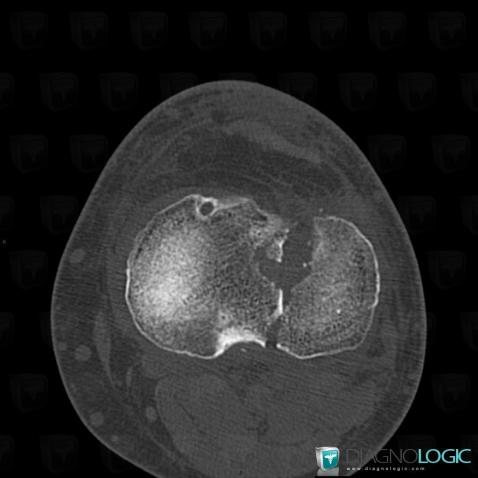

Fracture, Tibia - Proximal part, CT

- Diagnosis Fracture, Location(s) Tibia - Proximal part, with gamuts